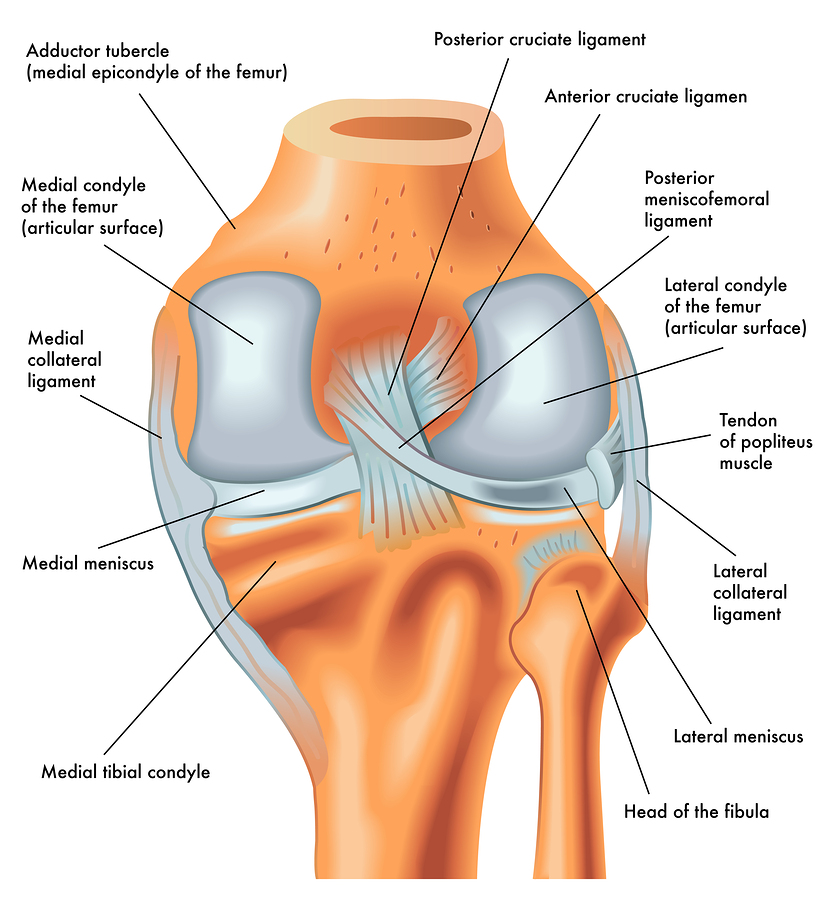

How much does it cost to repair a torn ACL in dogs. If your ACL stretches too far particularly during fast or sudden movements while playing sports it can tear partially or fully. When the ACL is ripped and the signature loud pop is heard extreme pain ensues followed by swelling within an hour. This machine creates pictures that look like slices of the knee. Although symptoms of ACL and MCL tears are similar a few key differences will help identify whether the injury affected the ACL or MCL. This is what a Torn ACL looks like.

The MRI machine uses magnetic waves rather than X-rays to show the soft tissues of the body. There was a loud snap. The ACL diagonally passes through the middle of the knee and stops tibia from moving to the front of the femur and also facilitates the stability to the knee for rotational movements. Heres a fascinating look i. This is what a Torn ACL looks like.

Torn ACL in the knee is a cut or tear of the ACL ligament at the knee. There was a loud snap. The MRI machine uses magnetic waves rather than X-rays to show the soft tissues of the body. Torn ACL in the knee is a cut or tear of the ACL ligament at the knee. Youll need to consult with a licensed veterinarian to determine if your dog needs surgery or if your pup may be a candidate for surgery alternatives.

The knees four main ligaments tether the tibia shin bone to the femur thigh bone. How does an ACL tear feel after a week. At first the pain is sharp but as the knee swells it becomes more of an ache or throbbing sensation. The pictures show the anatomy and any injuries very clearly. There was a loud snap.

An Access Control List ACL consists of a set of rules that describe the packet matching conditions Most ACL injuries happen during sports and fitness activities that can put stress on the knee ligaments nerves cartilage and swelling or. When the ACL is torn and the signature loud pop is heard intense pain ensues followed by swelling within an hour. Magnetic resonance imaging MRI is probably the most accurate test for diagnosing a torn ACL without actually looking into the knee. The knees four main ligaments tether the tibia shin bone to the femur thigh bone. The autograft then courses upwardly and backwardly in front of the posterior cruciate ligament 2.

Friendly mamma Cat needing a home Interested call 1 501 286-3722. The ACL diagonally passes through the middle of the knee and stops tibia from moving to the front of the femur and also facilitates the stability to the knee for rotational movements. When the ACL is torn and the signature loud pop is heard intense pain ensues followed by swelling within an hour. The pictures show the anatomy and any injuries very clearly. Arthritis shows up on a plain x-ray.

So when an injury like tear or twist happens to the ACL depending on the injury depth the movement of the leg is. Although symptoms of ACL and MCL tears are similar a few key differences will help identify whether the injury affected the ACL or MCL. The anterior cruciate ligament or ACL is in. The pictures show the anatomy and any injuries very clearly. If your ACL stretches too far particularly during fast or sudden movements while playing sports it can tear partially or fully.

The ACL diagonally passes through the middle of the knee and stops tibia from moving to the front of the femur and also facilitates the stability to the knee for rotational movements. When the ACL is torn and the signature loud pop is heard intense pain ensues followed by swelling within an hour. Moderate-to-severe pain is common. Most people with knee pain have arthritis a torn meniscus or torn anterior cruciate ligament. The autograft then courses upwardly and backwardly in front of the posterior cruciate ligament 2.